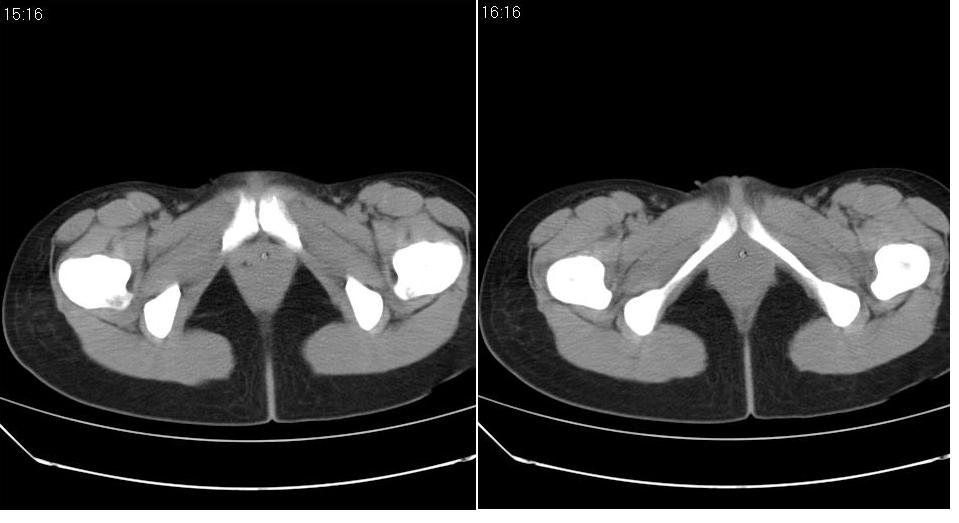

标题: CT22811:女 36岁,B超提示右侧附件囊性占位。 [打印本页]

标题: CT22811:女 36岁,B超提示右侧附件囊性占位。

右侧卵巢囊肿

手术结果证实为右侧输卵管囊肿。

输卵管囊肿罕见,从影像上无法同卵巢囊肿区分。

输卵管囊肿一般是指输卵管受病原体感染以后,由于白细胞的浸润形成内膜肿胀、间质水肿、渗出,输卵管粘膜上皮脱落,如果输卵管急性期炎症没得到及时有效的治疗就形成了输卵管积脓。输卵管积脓在炎症消退后,脓液逐渐被吸收,腔内积液由脓性变为浆液性,则成为输卵管囊肿。

还是报右侧附件区良性囊性占位性改变       至于输尿管或卵巢囊肿不太好鉴别